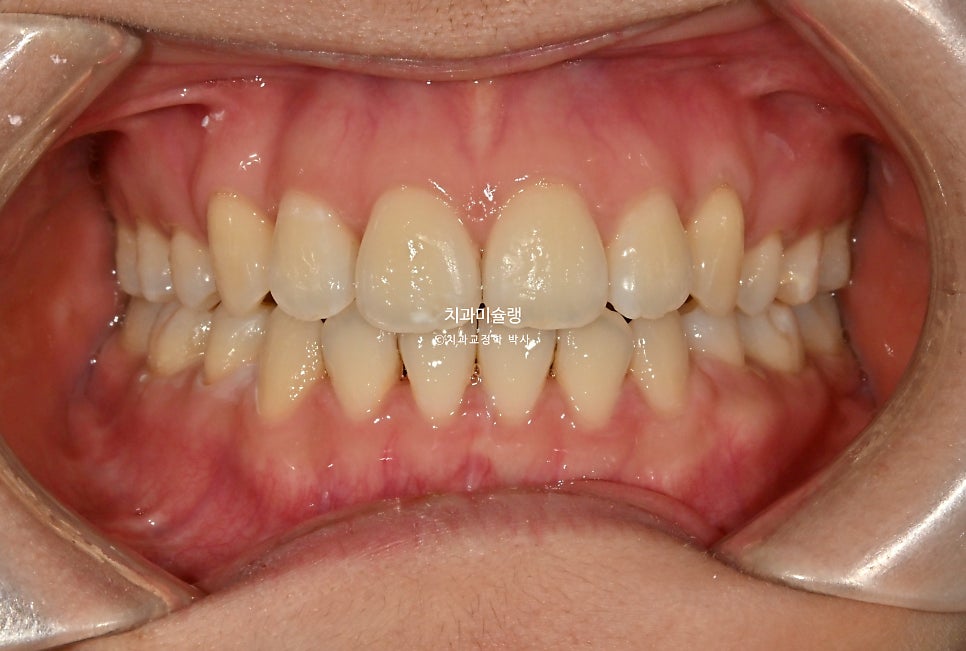

2026년 2월 치료 완료

18개 추가장치를 모두 낀후 2026년 2월, 드디어 치료를 마무리 했습니다.

2년 5개월의 교정 기간동안 결혼, 임신 출산까지 해내신 환자분.

어금니 교합은 좋으며 1급 교합관계를 보입니다.

치료 결과 비교

이제 전후비교 보겠습니다.

유지장치까지 잘 들어간 모습입니다.

치료 전반에 걸쳐 치간삭제는 하지 않았습니다.